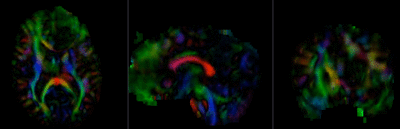

this is the fixed T1 reference image. All images are aligned into this space this is the FLAIR scan, to be registered with the T1 lleft this is the T1Gd image, serves as reference to which all others are aligned lleft this is the DTI tensor image, to be registered with the T1

DTI tensor

This is a typical example of DTI processing. Goal is to align the DTI image with a structural scan that provides accuracte anatomical reference. The DTI contains acquisition-related distortion and insufficient contrast to discern anatomical detail. For treatment planning and evaluation, location of functionally critical fiber tracts relative to the pathology is sought.

DTI aligned with T1Gd DTI aligned with T1Gd

DTI deformation applied (before/after registration DTI deformation applied (before/after registration